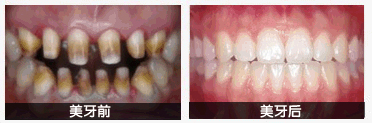

中韩·唯美口腔牙齿美容前后对比图